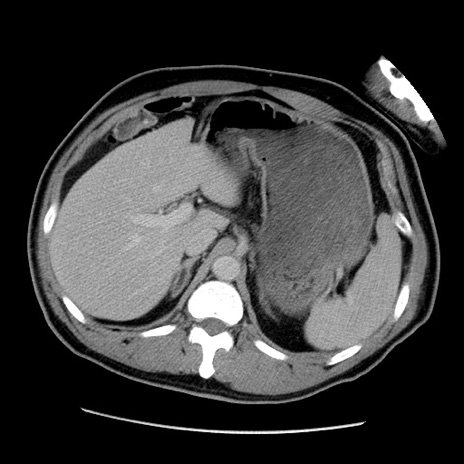

冠状断像

【症例】50歳代男性

【主訴】腹痛

【現病歴】AVMからの被殻出血のため回復期リハ病棟入院中。 本日午後3時頃急に下腹部痛が出現した。

【既往歴】AVM、被殻出血、虫垂炎、高血圧

【身体所見】意識晴明、左半身不全麻痺、会話の理解は良好、36.5°C、腹部:膨隆、全体に板状硬、下腹部正中に圧痛点あり、反跳痛-、筋性防御不明、右下腹部にope scar

【データ】WBC 9400、CRP 0.06